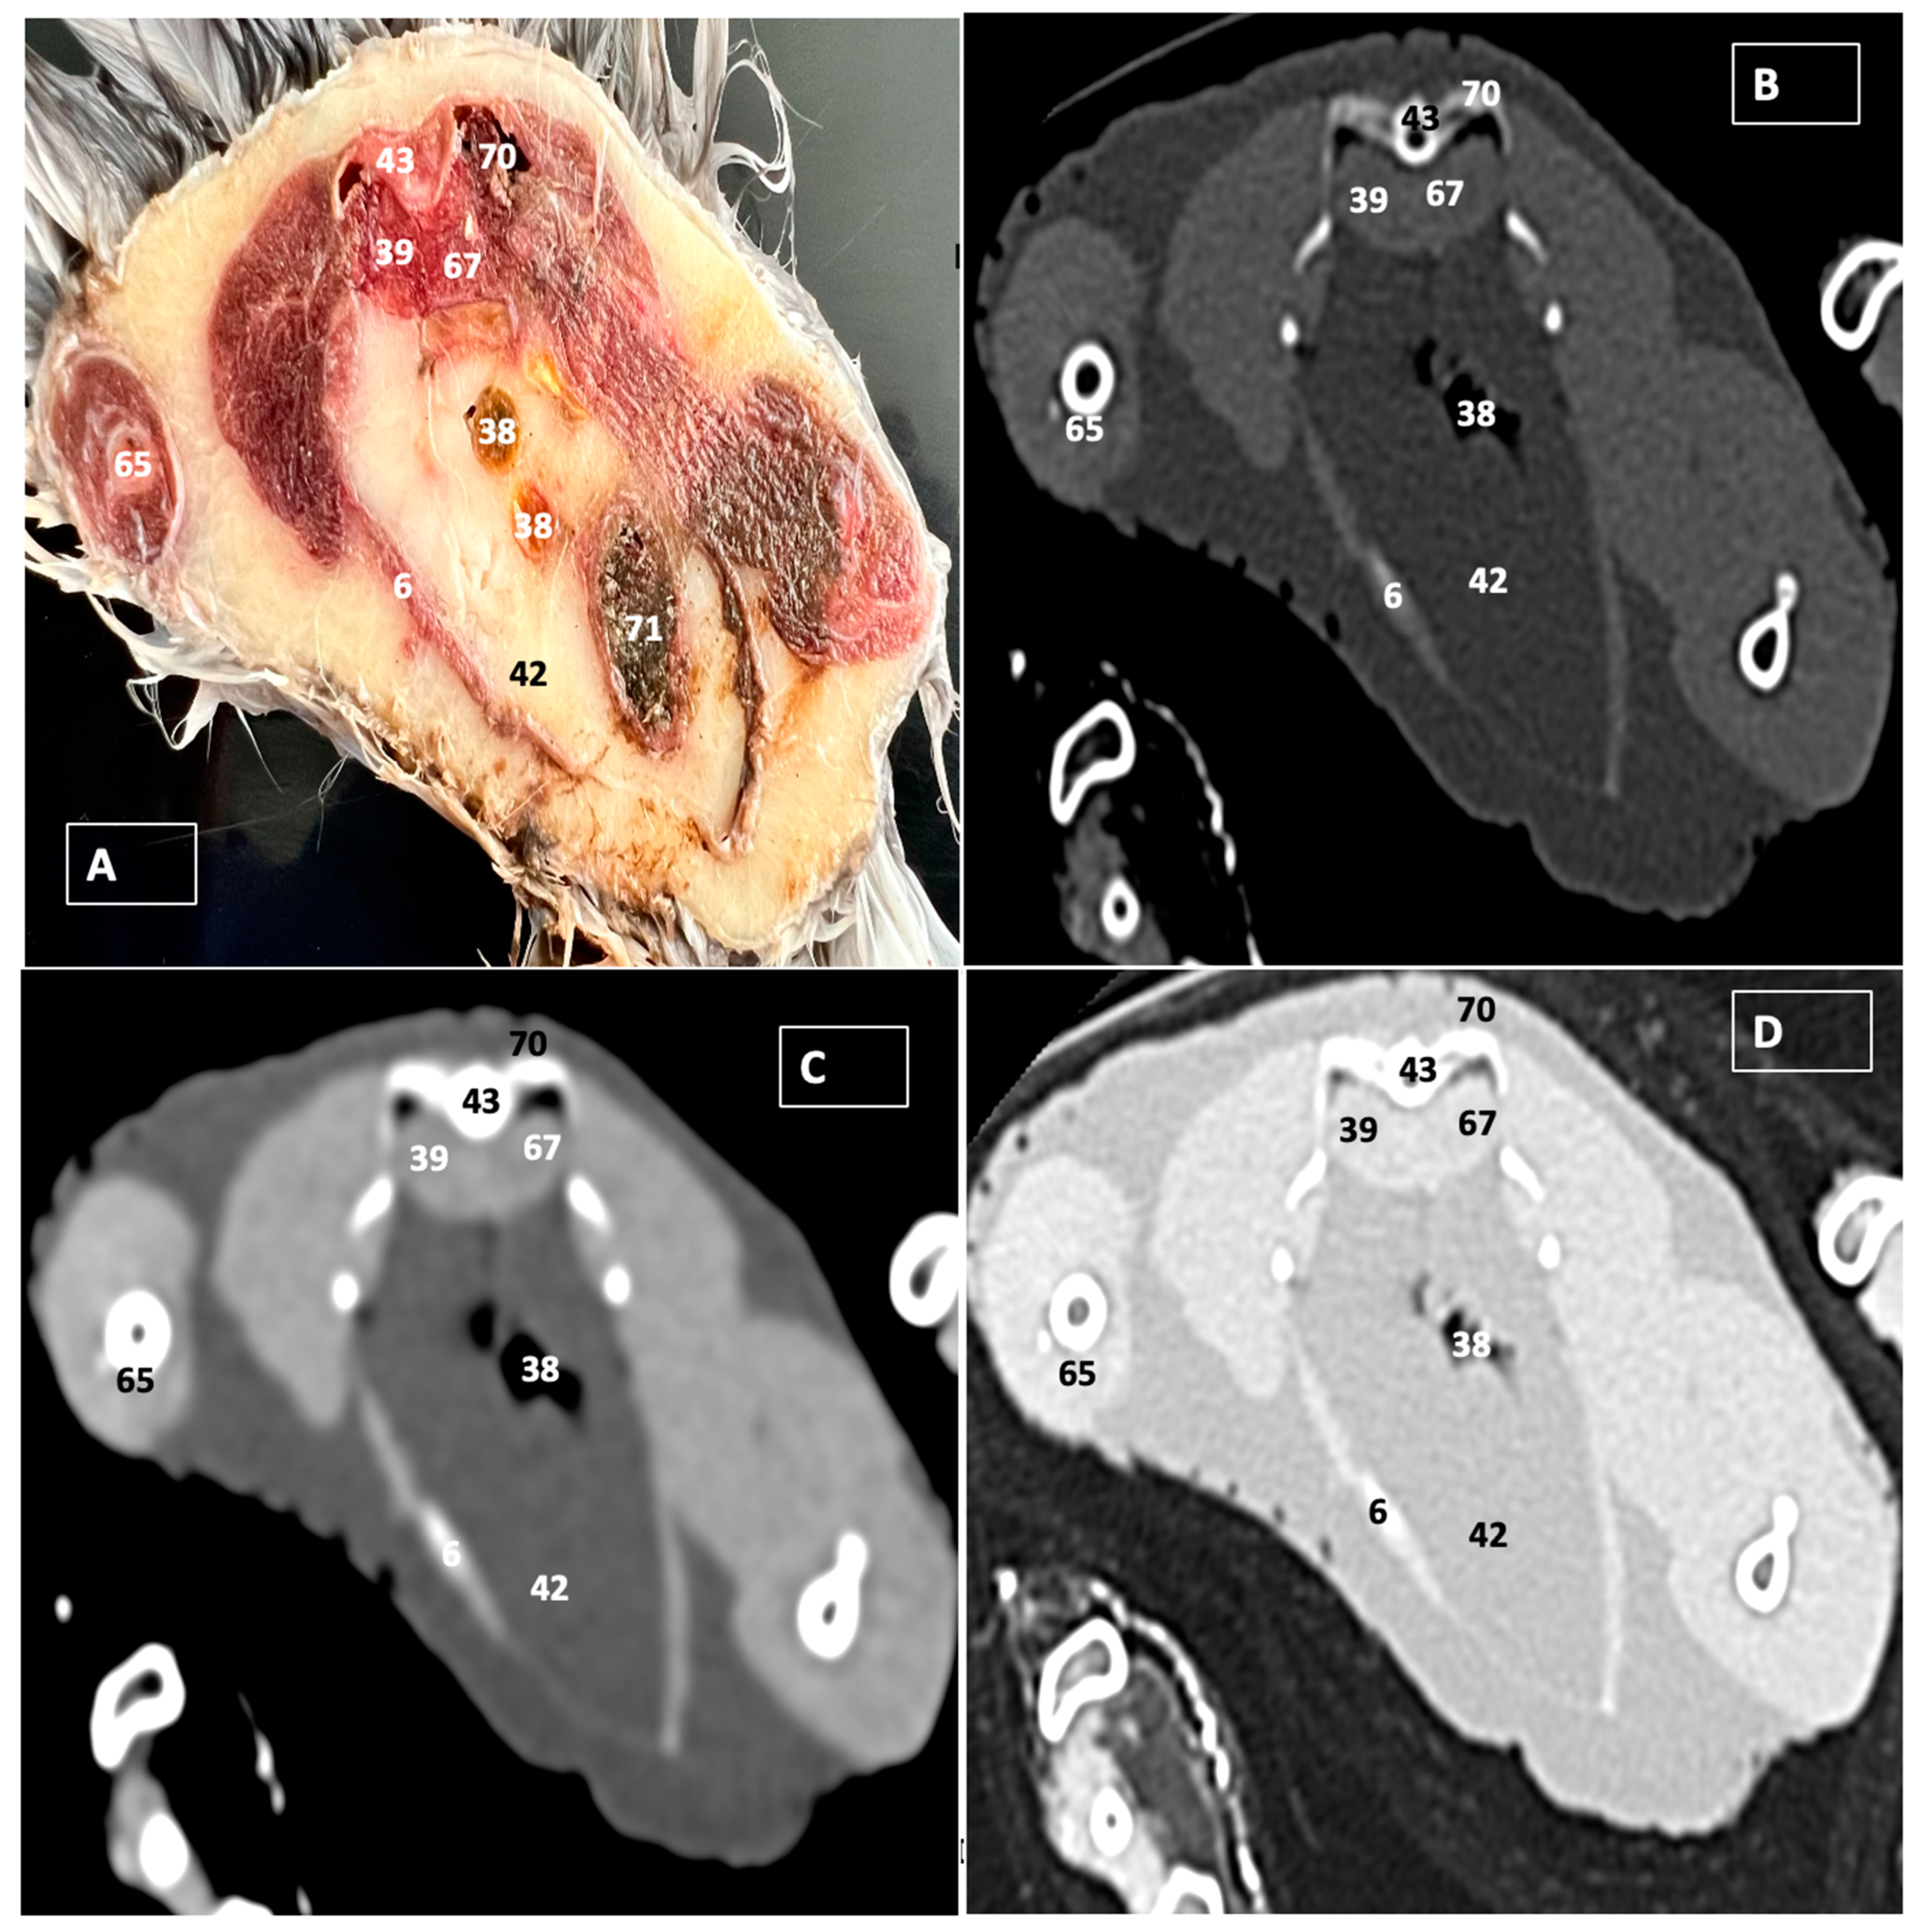

3.1. Anatomical Dissections and Cross-Sections

3.2. Computed Tomography Images